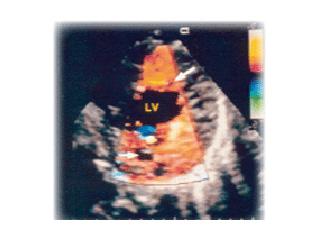

In this disorder, echocardiography demonstrates a thin epicardium with extremely hypertrophied endocardium and prominent trabeculations with deep recesses. These features tend to be apically localized.